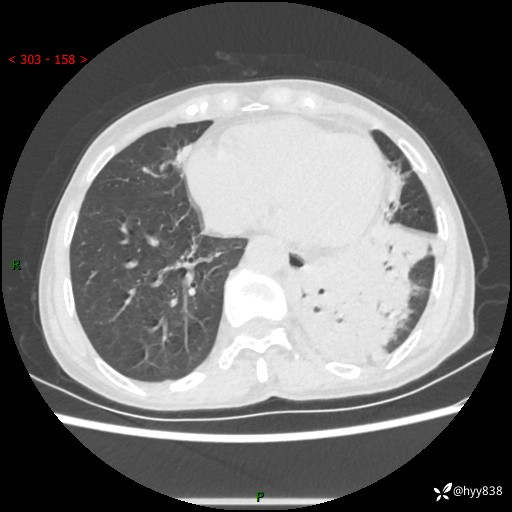

胸部CT平扫+增强